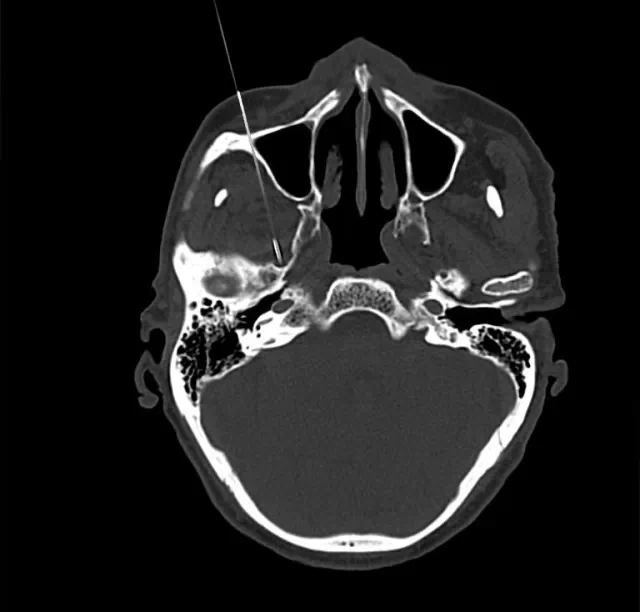

四川奥斯迪康骨医院治疗方法:CT引导射频热凝术

治疗原理:三叉神经为感觉神经,其中神经纤维(AA纤维和AB纤维)能耐受较高温度,而痛觉神经纤维不能耐高温,CT引导三叉神经热凝术选择破坏痛觉纤维,使患者疼痛治愈。